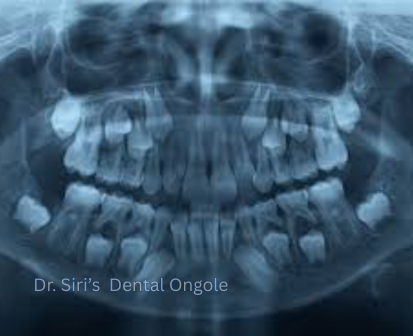

Dental X-Rays

Dental X-rays are an essential diagnostic tool that help dentists see what is not visible during a routine examination. They reveal hidden problems such as cavities between teeth, bone loss, infections, and impacted teeth, allowing for early and accurate treatment.

At Dr. Siri’s Dental, Ongole, we use safe and modern digital X-ray technology that minimizes radiation exposure while providing clear and detailed images for precise diagnosis and treatment planning.